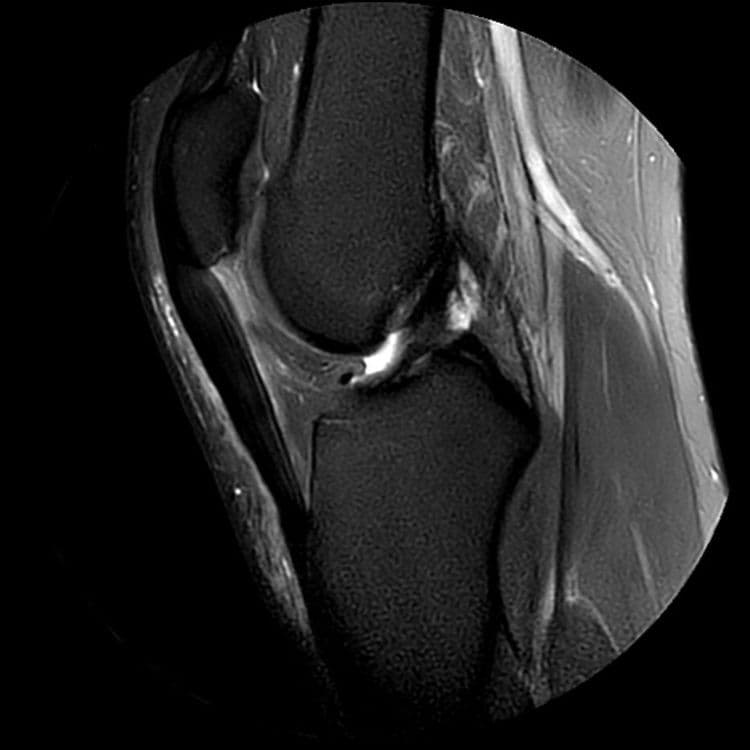

Rupture partielle du ligament croisé antérieur aux dépens du faisceau antéro-médial, avec aspect continu du faisceau postéro-latéral.

MRI